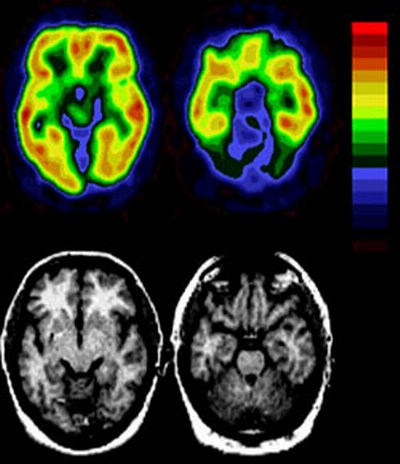

Setelah melakukan penelitian, akhirnya para ilmuwan menemukan sebuah kesimpulan. Bahwa, otak bagian depan yang terletak pada ubun-ubun itulah yang paling bertanggung jawab terhadap terjadinya dusta.

Al-Quran memberikan sifat كاذبة خاطئة (mendustakan lagi durhaka). Kenyataan seperti inilah yang ditemukan para ilmuwan pada masa sekarang ini dengan menggunakan pemindaian resonansi magnetik.